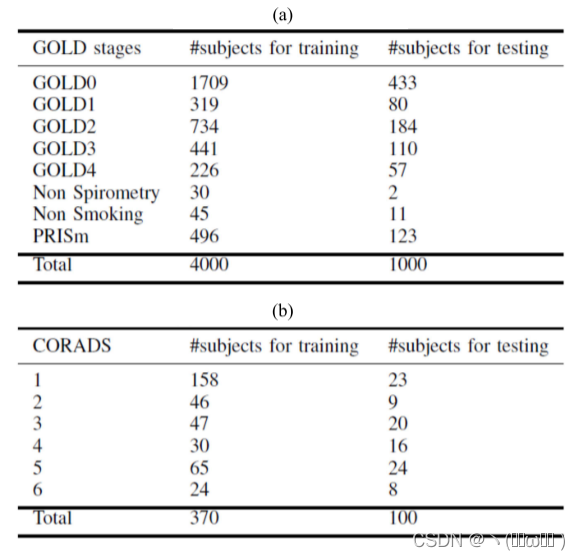

另一个数据集来自荷兰奈梅亨的 Radboud 大学医学中心。 2020 年 3 月 18 日,该机构实施了低剂量非增强 CT 方案,所有到达医院的疑似 COVID-19 疾病患者和被认为可能患有 COVID-19 的住院患者都接受了 CT 检查。 根据当地指南,我们只包括不反对将其扫描用于研究目的的受试者的扫描,并且我们使用匿名数据。 研究使用许可是从我们的审查委员会获得的(文件号 CMO 2016-3045,项目 20027)。 打算通过荷兰国家 COVID-19 数据库共享这些扫描。 我们随机选择了 470 名受试者,并通过在一项研究中选择最小层厚的 CT 扫描,对每位受试者使用一次扫描。 扫描的像素间距在 0.5 毫米到 0.9 毫米之间,切片厚度为 0.5 毫米。 使用范围为 10mA 至 493mA 的 X 射线管电流和 100 或 120kVp 的管电压进行扫描。 重建中的卷积核是肺核(FC83,FC86)。 其中 370 次扫描用于训练,另外 100 次用于测试。 有关 COPD 集的训练和测试集的 GOLD 阶段分布以及 COVID-19 集的 CO-RADS 分数 [1] 的分布,请参见表 I。 CO-RADS 评分定义了对 COVID-19 的怀疑程度,并从放射学报告中提取。 在数据匿名化时无法获得逆转录聚合酶链反应 (RT-PCR) 测试的完整个体结果,但已知大多数测试案例对 COVID-19 呈阳性(这些测试案例重叠 与[1]中使用的数据)。 从两个训练数据集中,我们选择了 100 个扫描作为 COPD 集的验证集,我们从 COVID-19 集中选择了 50 个扫描进行验证,用于重新训练所有模型。

表 I:这项研究所使用的两组数据的特征。(a)列出了GOLD阶段和其他阶段的分布,参见COPD数据集中的[32]。(b)给出训练集和测试集的合作分数分布[1]。CO-RADS 得分1-6表明对2019冠状病毒疾病阳性疾病的怀疑程度,从非常低、低、模棱两可、高、非常高,分别从反转录聚合酶链式反应(RT-PCR)测试中确认为阳性